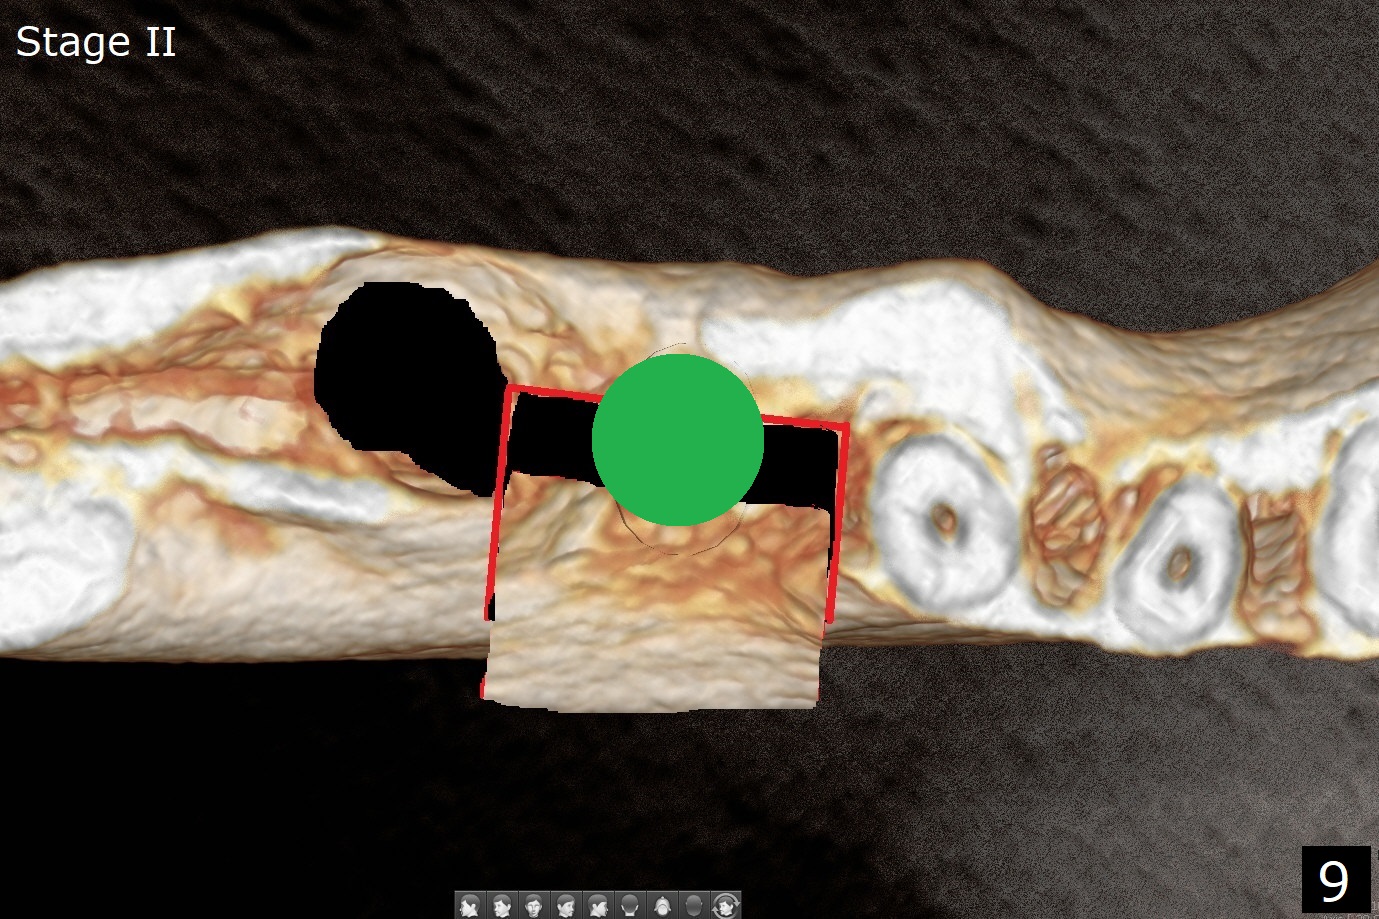

Several months post #31 socket preservation, the narrow ridge of #30 (Fig.1 (CT 3-D occlusal view), 6 (coronal section)) will be exposed with a crestal and 2 oblique incisions, followed by osteotomy with a 2 (2.2) mm drill (green) and a surgical guide. A crestal transverse cut will be conducted using a surgical fissure bur (Fig.2 red), followed by 2 vertical cuts (Fig.3,4 (3-D X-ray mode, buccal view) and an apical transverse one (Fig.5,6). The incision will be closed. Three weeks later, a crestal incision will be made. The buccal plate will be fractured and pushed buccal (Fig.7,8 arrow) using chisel (yellow). The guide will be reseated for osteotomy, implant placement (Fig.9 green) and bone graft. In fact there is not much problem when the osteotomy moves lingual.